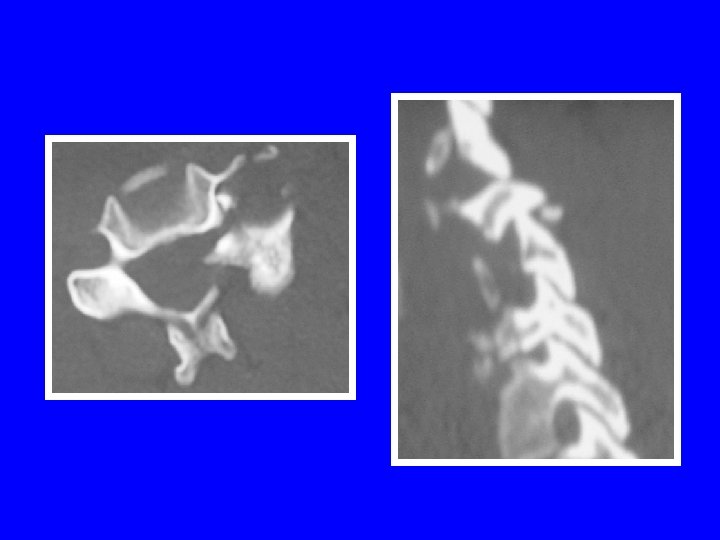

FRACTURE SEPARATION D ’UN MASSIF ARTICULAIRE Retentissement foraminal++

LESIONS MIXTES: LA FRACTURE TEAR DROP Schneider et Kahn (1956) Mécanisme en flexioncompression trait de fracture frontal trait de fracture sagittal trait de fracture lamaire lésions ligamentaires LLV, LLD, disque

Prédomine en C 5 (65%) Neuroagressivité++ stade 3 de Allen: 25% (médullaire) stade 5 de Allen: 91% (médullaire) Instabilité selon l ’atteinte discoligamentaire Les disques sus et sous-jacents peuvent être atteints Double tear drop

LESIONS MIXTES: LA FRACTURE TEAR DROP Allen (1986): 5 stades stade 1: aspect émoussé du coin antéro-inférieur stade 2: perte de hauteur partie antérieure du corps stade 3: trait de fracture en goutte d ’eau stade 4: stade 3+ déplacement postérieur <3 mm stade 5: stade 3+ déplacement postérieur >3 mm

Tear drop stade 3 Tear drop stade 4